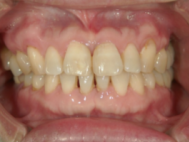

症例写真

インプラントは【第二の永久歯】とも言われています。

虫歯や歯周病、外傷などによって抜けてしまった歯にかわって、咬み心地や見た目を回復します。歯が無くなって、下記のように諦めている事や悩んでいる事はありませんか?